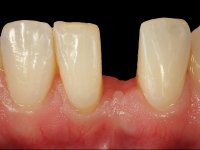

In the dental lab, a Maryland bridge with a zirconia framework veneered with a feldspathic ceramic was built. The wings internal surface also had a very thin coating of a zirconia adhesive to allow its bonding to the abutments enamel. This Maryland bridge tried to join the mechanical strength of the framework, to the bonding of the ceramic to the enamel, and to the aesthetics’ of the zirconia’s veneering with a feldspathic ceramic.

Then, this Maryland bridge was bonded to the abutments.

This rehabilitation proved to be a minimal invasive procedure, affordable and aesthetically acceptable.